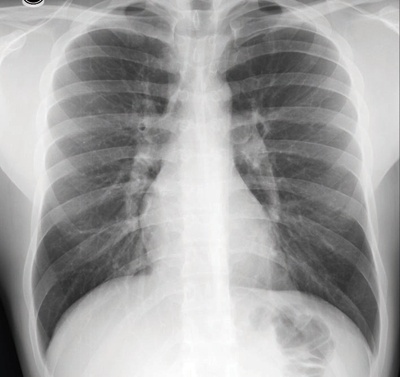

يتم تشخيص الالتهاب الرئوي بأخذ تاريخ المرض والفحص السريري للمريض إلا أن الفحص المؤكد للتشخيص هو تصوير الصدر بأشعة إكس, حيث يثبت وجود ومكان الالتهاب ونوعه إن كان التهابا رئويا مقطعيا أو التهابا رئويا شعبيا.

بالتأكيد إذ يأتي بعد الخطوات السابقة دور الفحوص الطبية، كالأشعة السينية، وفحص البلغم تحت الميكروسكوب لتحديد نوع الجرثومة إن أمكن، كما يتم عمل مزرعة للبلغم لمعرفة نوع العدوى، كما يتم عن طريق فحص كريات الدم البيضاء التعرف على مدى قوة الالتهاب ومدى قدرة الكريات البيضاء على مقاومة المرض. كما يتم إرسال الدم للفحص الميكروسكوبي ولعمل مزرعة لتحديد نوع البكتيريا أو أي نوع آخر من الجراثيم مسبب المرض. وعند ظهور الجرثومة في مزرعة الدم، فذلك يعني أن البكتيريا تحركت من الرئتين إلى الدم.